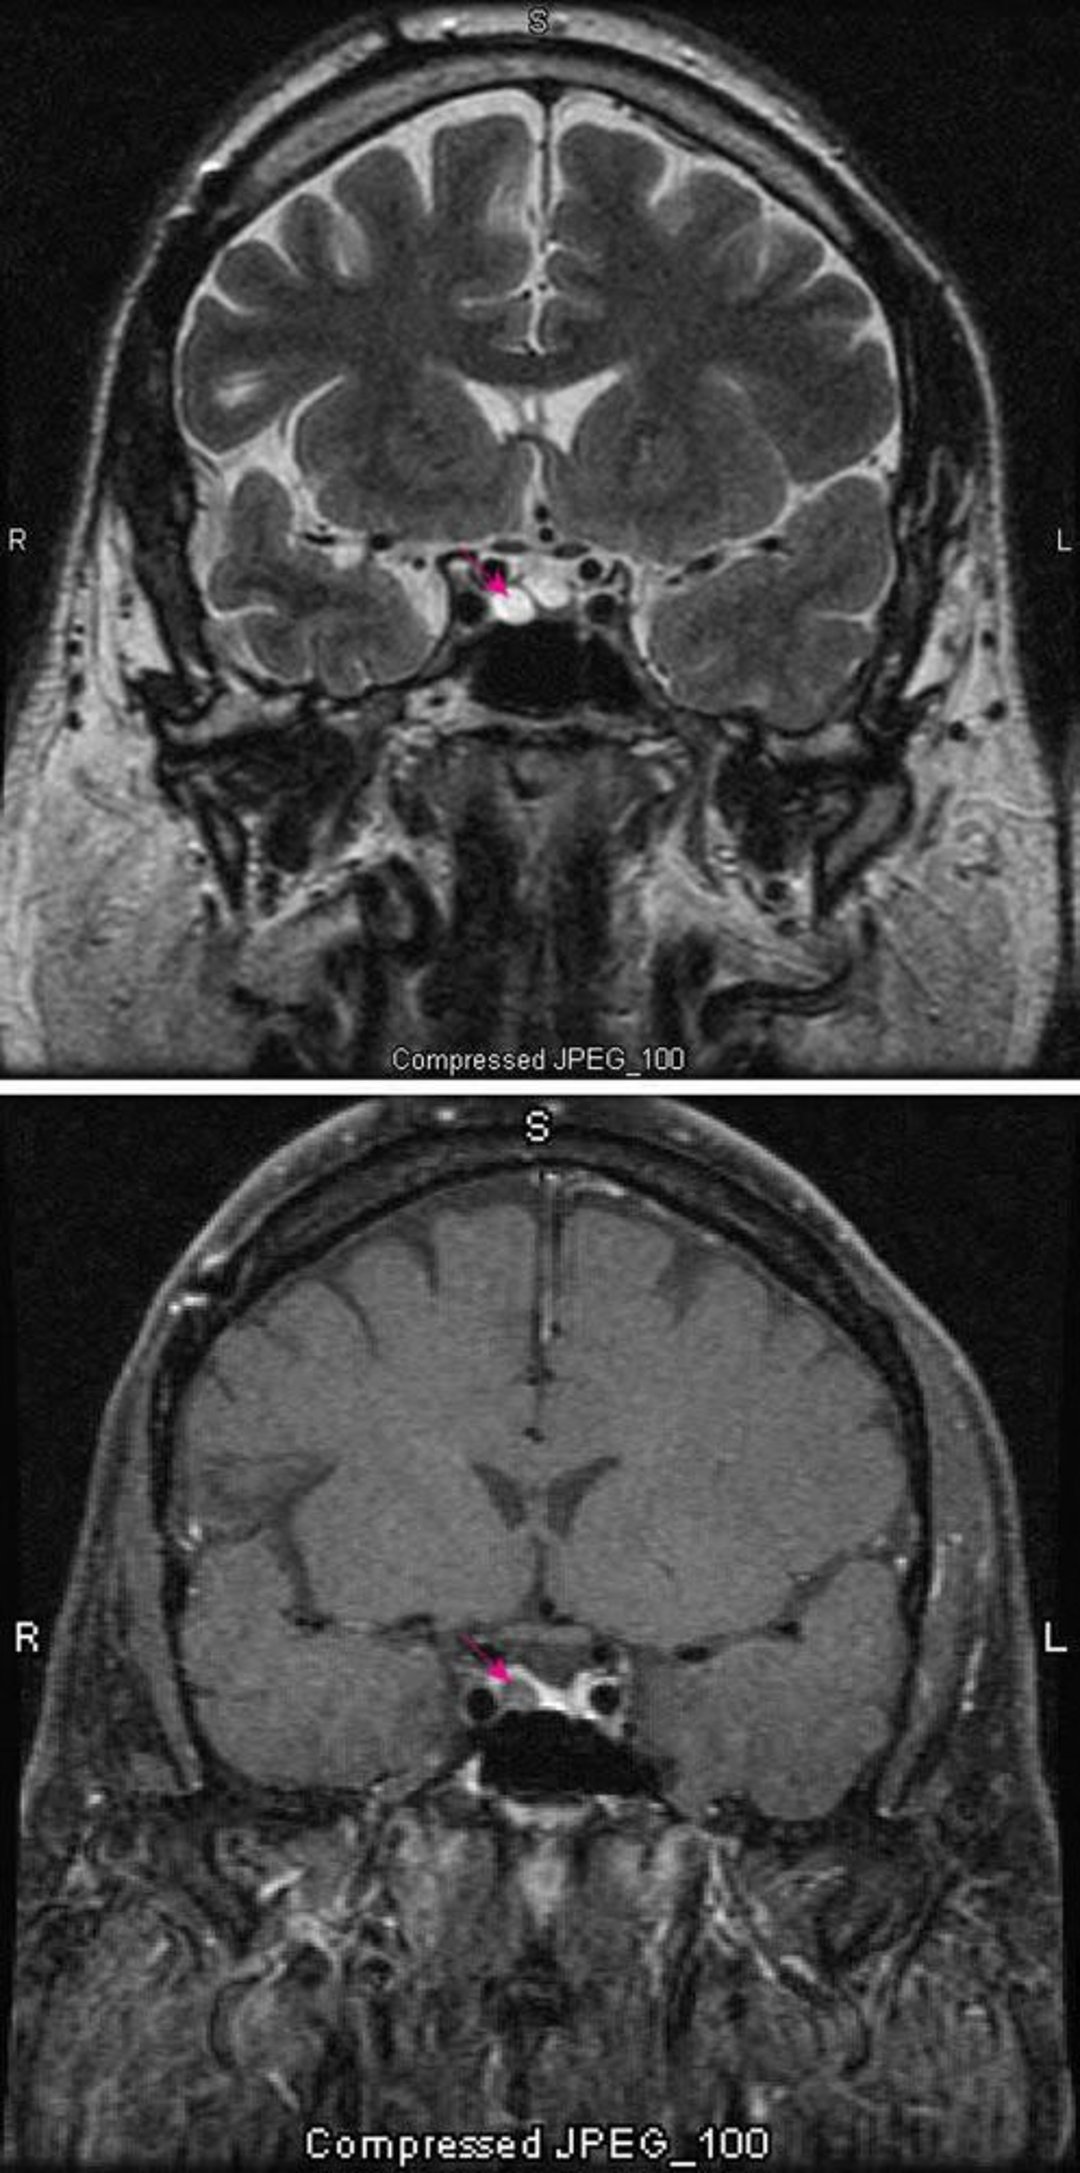

Микроаденома гипофиза

На T2-взвешенном изображении МРТ (вверху) показана микроаденома гипофиза (красная стрелка). Использование контрастирования (внизу) обычно выделяет контуры гипофиза (красная стрелка). Аденома выглядит более светлой.

Images courtesy of William R. Shapiro, MD.